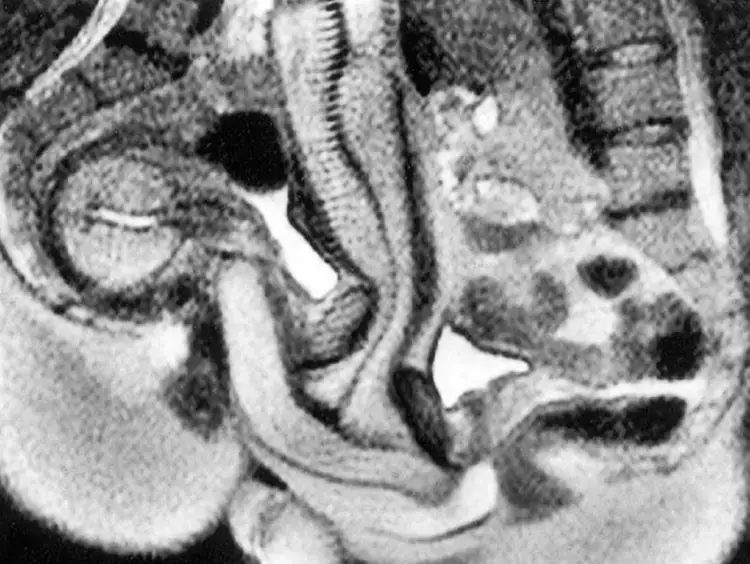

It was a smidge difficult to pull off as there wasn't a great amount of space in there, but they managed to get it on and learned that the gentleman's penis bends to fit the shape of the woman's vaginal canal during sex.

This contradicted beliefs from the likes of Leonardo da Vinci that the penis was basically just a straight cylinder during intercourse, but there were other findings from the experiments which scientists weren't able to explain.

Something else besides curved penises they found was that during all 13 instances of sex in an MRI machine, the woman's bladder would rapidly fill up.

He said: "In every final scan we could see a big, full bladder, even though most of the women went to the toilet before they went inside the MRI."